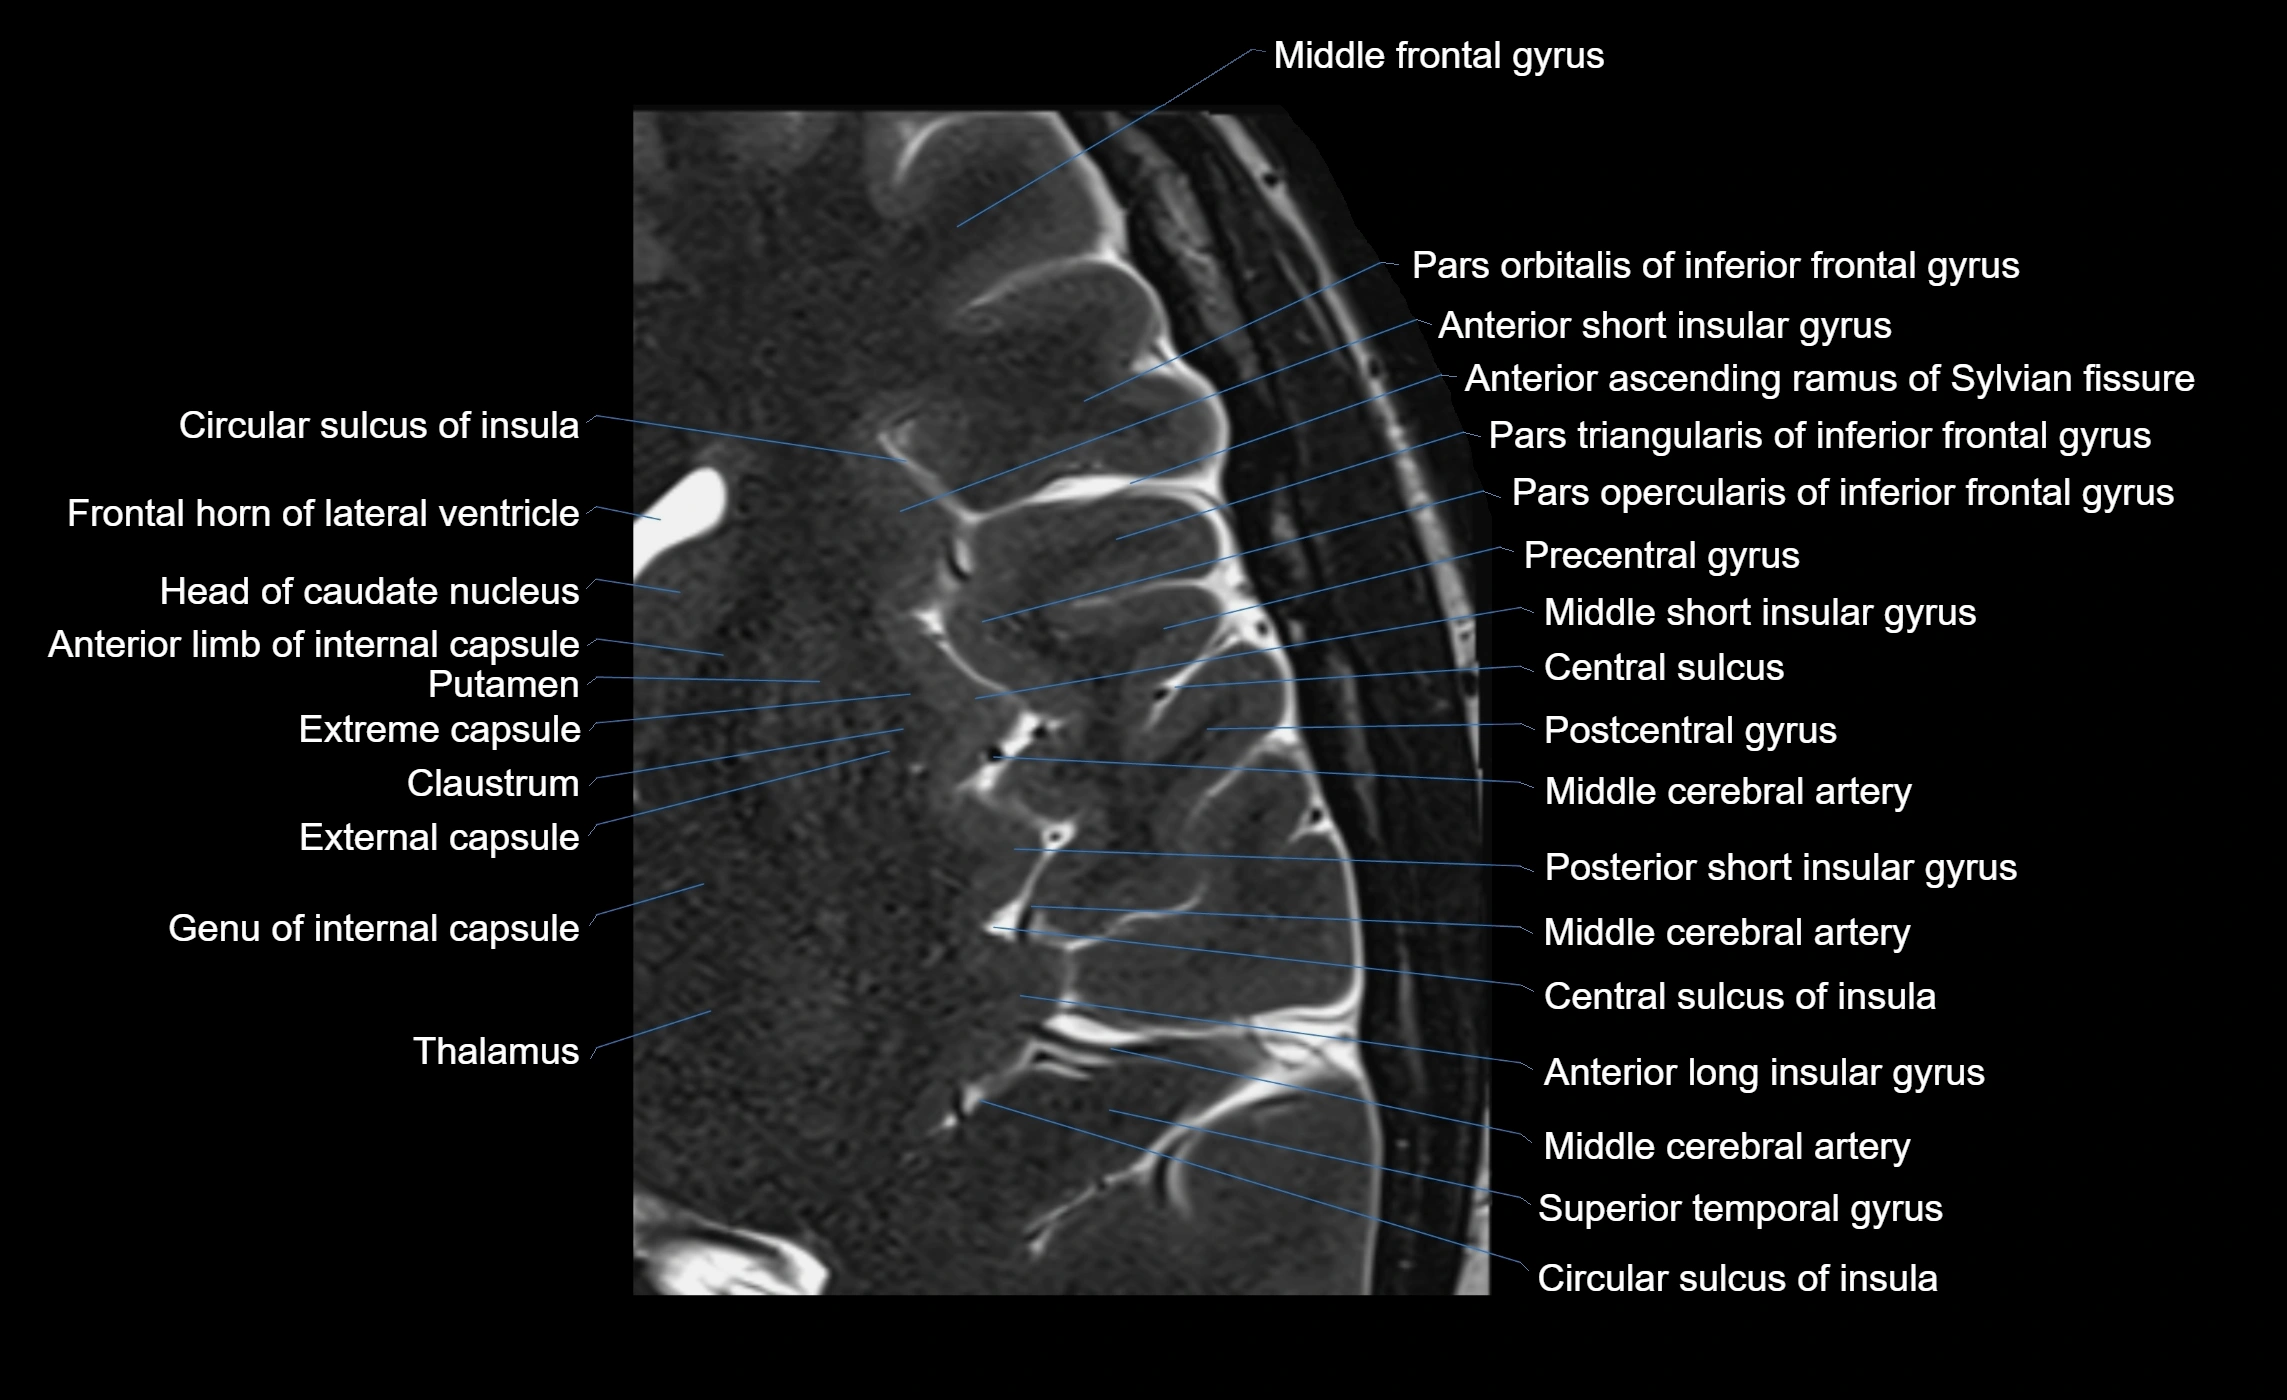

The anterior ascending ramus of the Sylvian fissure is a significant anatomical landmark in the lateral surface of the cerebral hemisphere. It represents one of the key branches of the Sylvian fissure (also known as the lateral sulcus) and plays an essential role in demarcating the boundaries between important cortical regions, notably within the frontal and parietal lobes. Understanding its anatomy and imaging appearance is crucial in neuroradiology, neurosurgery, and neuroanatomy for accurate localization and identification of adjacent brain structures.

• The anterior ascending ramus is a short, superiorly oriented branch that arises from the main stem of the Sylvian fissure.

• It projects upward (anteriorly and slightly dorsally) from the lateral sulcus into the inferior frontal gyrus.

• This ramus separates the pars opercularis (opercular part) from the pars triangularis (triangular part) of the inferior frontal gyrus.

• The anterior ascending ramus marks the boundary between Broca's area and adjacent cortical areas in the dominant hemisphere.

• T1-weighted imaging:

• The Sylvian fissure and its anterior ascending ramus appear as low-signal intensity (dark) CSF-filled clefts between the gyri.

• Clear demarcation between adjacent gray and white matter.

• T2-weighted imaging:

• The fissure, including the anterior ascending ramus, is hyperintense (bright) due to CSF signal.

• Better visualization of the separation between opercular and triangular parts of the inferior frontal gyrus.

• FLAIR imaging:

• The ramus is visualized as a linear dark space (suppressed CSF signal) between the surrounding cortex.

• Adjacent cortical and subcortical abnormalities (e.g., edema or gliosis) can be assessed relative to the ramus.